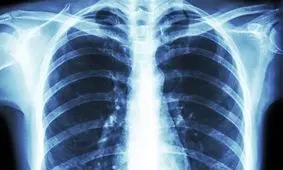

محققان دریافتند بقای سلولهای غیرطبیعی حاصل از ابتلا به کووید ۱۹ در ریه، مهمترین عامل بروز آسیبهای ریوی محسوب میشود.